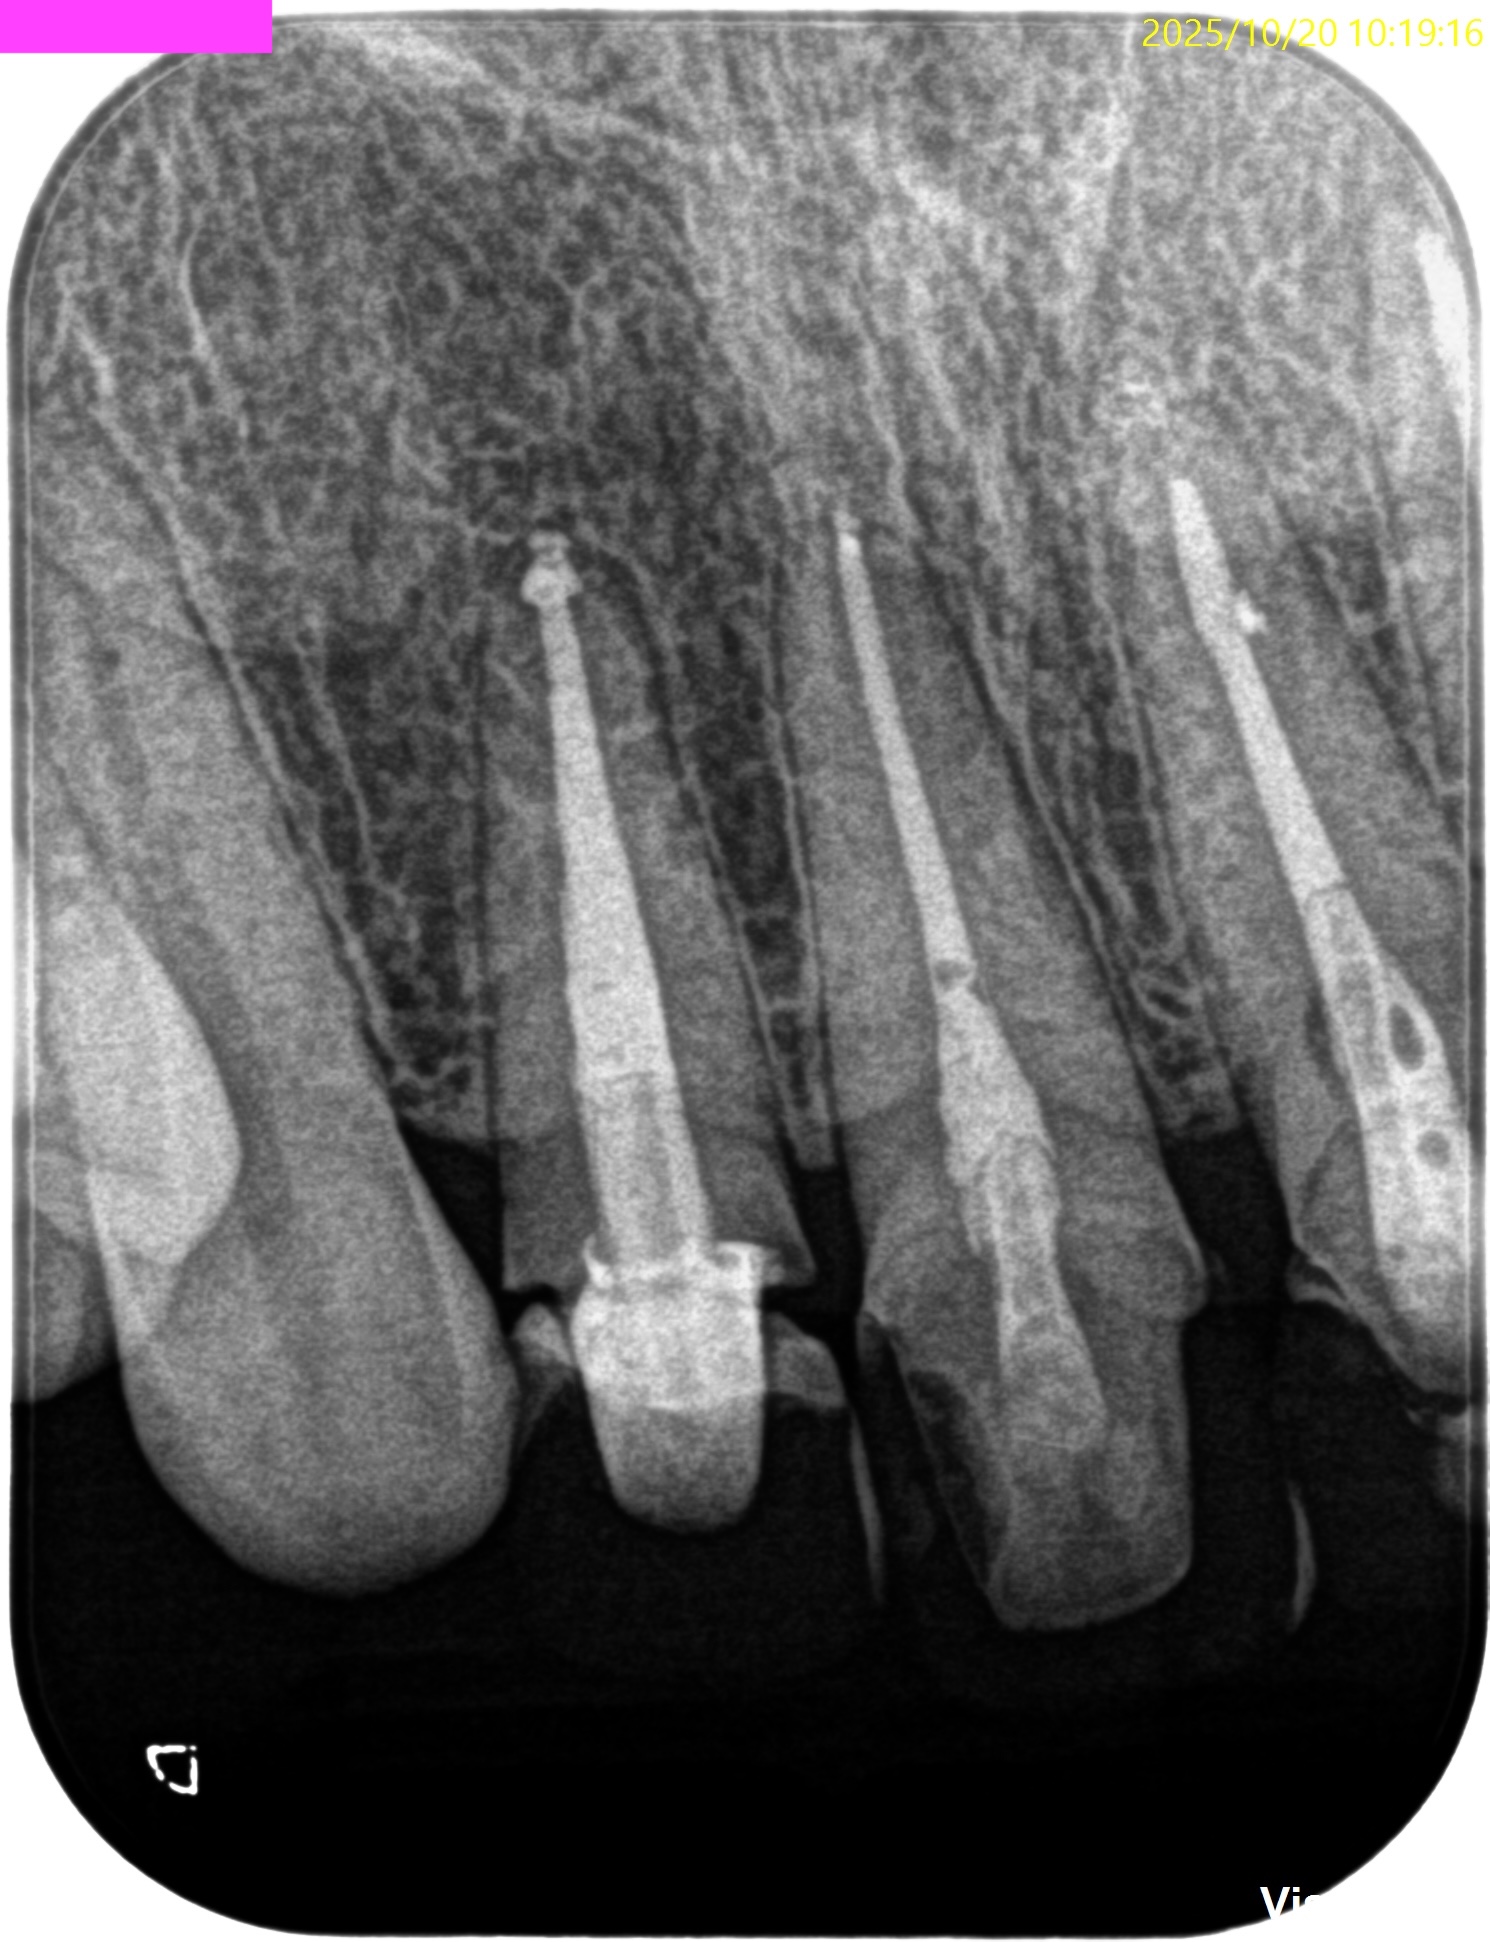

さておき、根充+支台築造後にPA, CBCTを撮影した。

#7

#10

ここから9ヶ月が経過し、かかりつけ医の先生からCBCTを評価してほしいとの依頼があった。

その結果が以下である。

さてこの画像からあなたは治癒傾向であるか否か?を判断できるであろうか?

そう。

よくわからないのである。

なので、実際に当歯科医院で検査も含めて評価することになった。